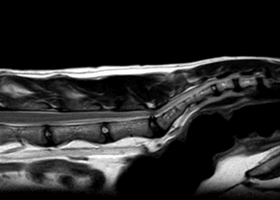

Mowgli, an 8-year-old male Main coon, was visited in our Neurology service for a chronic history of weakness affecting the hind limbs within the last 6 months, with an acute deterioration in the last week showing sporadic yelps when trying to jump. The neurological examination showed marked atrophy on hamstring muscles and severe discomfort on lumbosacral palpation. The MRI of the lumbosacral area documented a L7-S1 disc protrusion and dorsal indentation from the S1 dorsal lamina. Initially Mowgli was treated with steroid injections, but after an incomplete response to it, an L7-S1 dorsal laminectomy with discectomy were performed. After 2 months, Mowgli was free of pain and is increasing his strength on the hind limbs.